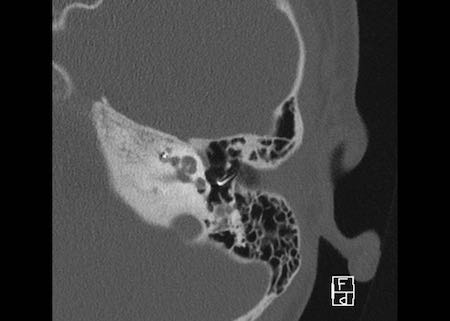

Bên trái là hình ảnh của một bệnh nhân có cống tiền đình giãn rộng hai bên.

Lưu ý rằng trụ ốc tai xương không quan sát thấy.

Bên trái là hình ảnh của một bé trai 5 tuổi với tình trạng nghe kém tiến triển hai bên.

Quan sát thấy cống tiền đình giãn rộng (mũi tên đen).

Ốc tai không có trụ ốc tai xương (mũi tên trắng).